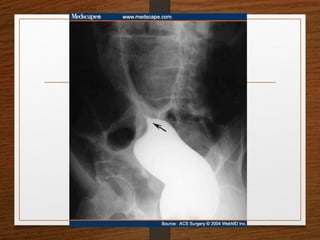

Doubt about the

diagnosis on the plain

radiographs

Contrast enema

• Features seen at the point of torsion include a

smooth, curved tapering of the colonic lumen, like a

hooked beak (the bird of prey sign)

• the mucosal folds often show a ‘screw’ pattern at the

point of twist

Doubt about the diagnosison the plain radiographs Contrast enema

Contrast enema • Featuresseen at the point of torsion include a smooth, curved tapering of the colonic lumen, like a hooked beak (the bird of prey sign) • the mucosal folds often show a ‘screw’ pattern at the point of twist